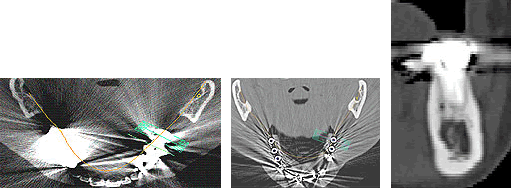

それでは実際にCTで撮影し、CTデータ3D立体構築画像変換検査したものがどう見えるのがご覧下さい。3次元でどこにどのようにインプラントを埋め込んでいけばいいのか、立体的に把握することができます。

下の写真をご覧下さい。

この写真は吉本歯科医院が手術前に行う、3D立体画像構築画面です。

患者さまの下顎の骨、そして神経が見えています。

吉本歯科医院でインプラント治療を行う患者さまの顎の状態は、CT画像だけでなくここまで立体化されたものが手術前には手元にあり、シミュレーションを行ってから実際の手術に入るような流れをとっております。

さて、この写真、黄色くうにょうにょとしているのが神経です。

本来骨の厚みがある患者さまの場合は神経の黄色い部分は骨の中に隠れているため3D立体画像で真上から見た場合かくれて見えません。

この方の場合、骨が神経の出口(オトガイ孔)まで磨り減ったためにこのように写ります。

さて、この神経は、ちょっと難しいんですが、下歯槽管(かしそうかん)神経といい神経、血管が入っているトンネルのような管です。

オトガイ孔はその出口です。

左右片側の下唇および、オトガイ孔の皮膚の知覚を司る神経です。

もし手術であやまってこの神経を損傷すると、下唇およびオトガイ部が麻酔がかかったようにしびれてしまいます。

インプラント手術をしたあと、「顔がしびれだした」といった症状はこの重要な神経に傷をつけてしまったことによって起こります。

この中で、インプラントにおいて執刀する歯科医師が最も留意しなくてはならないのが下歯槽管神経との距離なのです。

インプラント体で下顎骨の中を走る神経やオトガイ孔から出た神経を傷つける可能性があるため手術の前には必ずCT撮影をし、適正な長さのインプラント体の選択が必要となります。